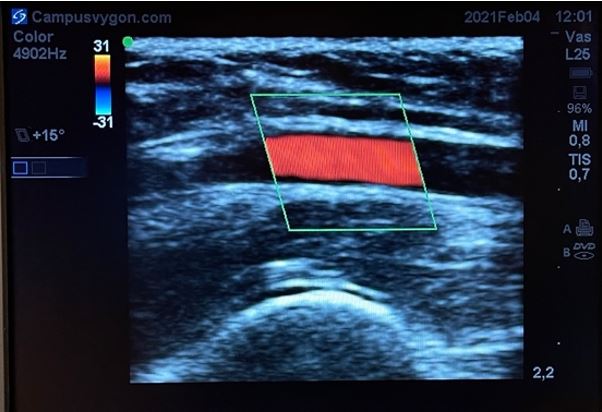

Cuando se estudia un vaso longitudinalmente con modo doppler color, puede ser útil emplear la opción de angulación de la caja de color, de tal manera que ahora los ultrasonidos se emitan angulados desde la sonda.

Esto facilita la identificación del vaso, sin tener que bascular la sonda en la piel del paciente. Teniendo en cuenta la posición de la muesca del transductor respecto a la pantalla y la angulación del ROI, podremos discernir la dirección del flujo estudiado mediante la misma regla: el flujo que se acerca al transductor será de color rojo y el que se aleja de color azúl.